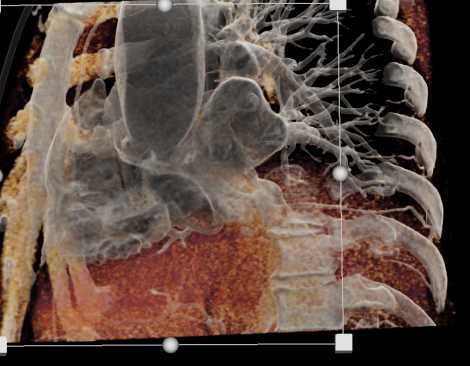

Primary Spindle Cell Carcinoma of the Right Ventricle